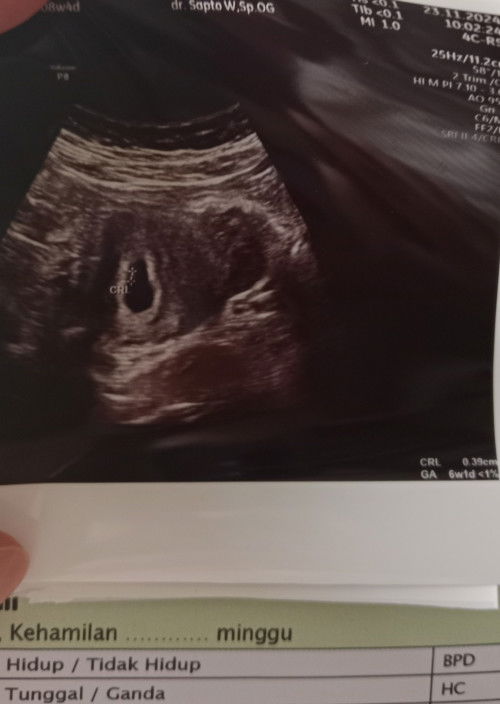

Hasil usg tidak sesuai dengan hpht Bunda² saya udh usg 2x Yg pertama saat 7w2d tapi ternyata pas di usg masih kantong Lalu tadi siang saya usg lagi uk 6w1d seharusnya kalau dari hpht 8w4d Alhamdulillah sudah ada janin dan djj nya, apa gpp ya bund? Bedanya 2 minggu :(#Sharing_dong_Bund #bantujawab